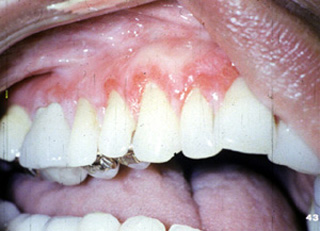

| A menudo

envuelve la encía y tiene una apariencia eritematosa y descamativa. Si

uno mira esta fotografía clínica, pueden verse áreas estriadas

blancas en la unión de la encía marginal con mucosa alveolar.

| Esta mujer 45

años de edad presenta úlceras

dolorosas de la encía alrededor de los dientes maxilares. El examen clínico

reveló la encía eritematosa con áreas

de ulceración. La higiene oral del paciente era buena y no había

evidencia radiográfica de enfermedad periodontal. No hay vesículas y ampollas; la piel no estaba involucrada. Esta condición era de un año

duración. No parecía cambiar en severidad durante ese tiempo.